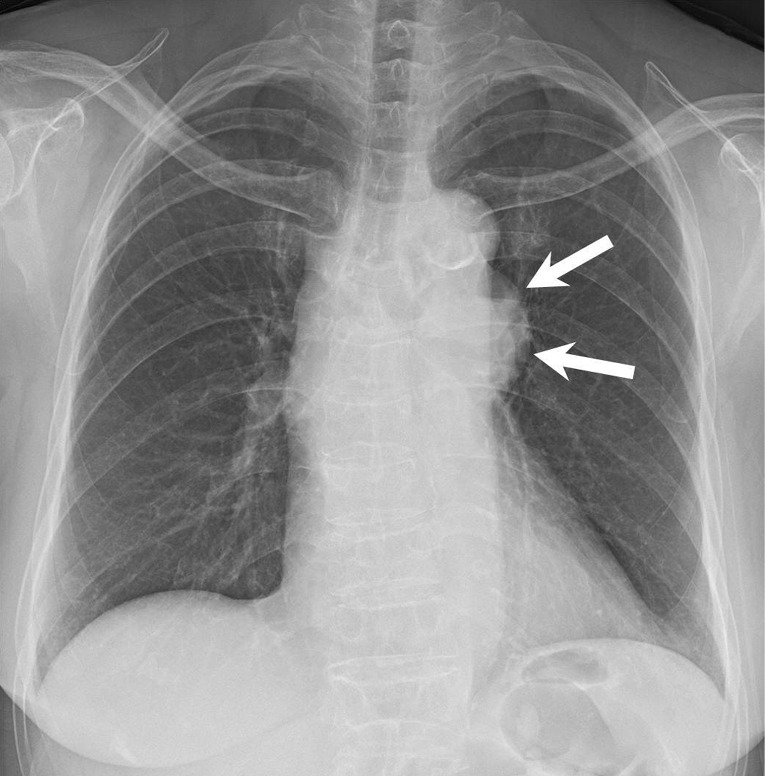

Case description: A 60-year-old woman visited Inje University Sanggye Paik Hospital with left hilar bulging detected on routine chest radiograph. A chest computed tomography (CT) scan revealed a 6 cm well-defined cystic mass with partial septation in the prevascular mediastinum. Thus, secondary thymic cyst was suggested. On the follow-up chest CT scan taken 3 months later, the size of the thymic cyst decreased, while the solid portion increased slightly, suggesting the potential presence of malignancy. Consequently, surgery was conducted. Adhesion to the lung and aorta was observed, but they were relatively well separated. The pathological findings revealed a partially ruptured thymic cyst with fat necrosis and multifocal granulomas.